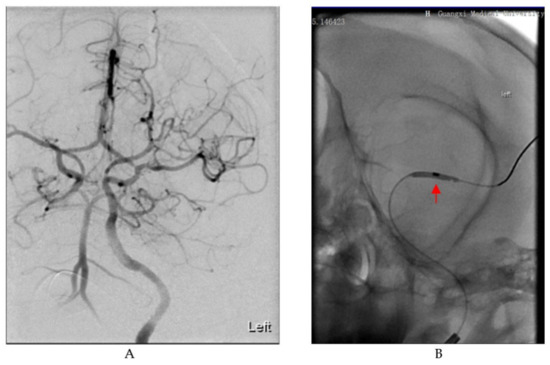

2.2.1. Middle Cerebral Artery Occlusion (MCAO) Ischemic Stroke Model

3.1. General Results of the Stroke Model and MRI Assessment